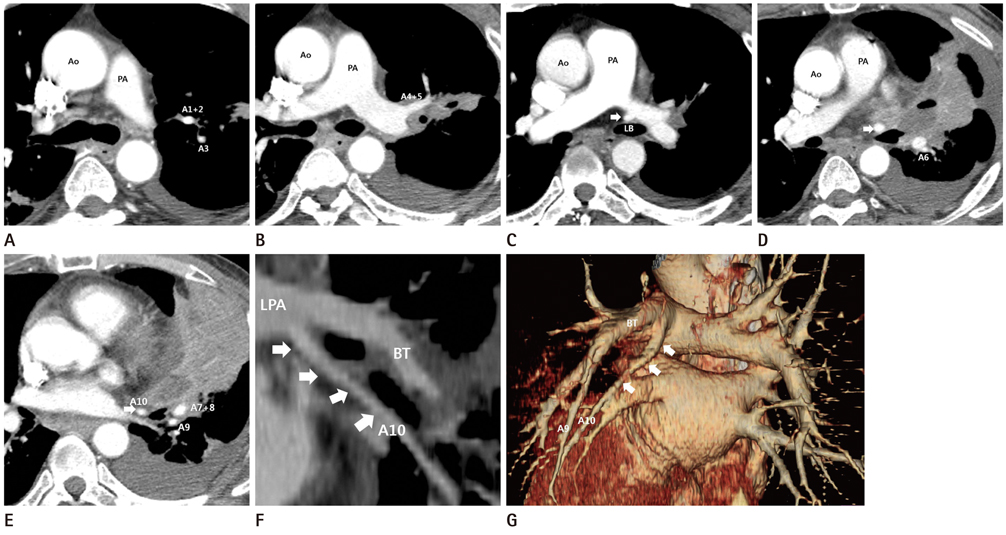

Unusual Anatomical Variant of the Left Posterior Basal Segmental Pulmonary Artery: CT Findings

- To avoid vessel injury during minimally invasive surgery of the lung, exact knowledge of the pulmonary vasculature is important to surgeon. In this report, we present the case of unusual anatomical variant of the left posterior basal segmental pulmonary artery, arising from the left main pulmonary artery. This anomaly is rare but easily overlooked during interpretation of CT scans, potentially resulting in serious vessel injury during minimally invasive surgery.